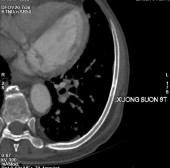

Hình B. Hình ảnh chụp CT sau điều trị 6 tháng

Sau 36 tháng điều trị, bệnh nhân xuất hiện tiểu máu, đau cột sống thắt

Bệnh nhân được xét nghiệm nồng độ PSA 631,3 ng/mL, fPSA 95,75

ng/mL, Testosterone 0 ng/dL.

Bệnh nhân được chụp cắt lớp vi tính toàn thân, kết quả:

- Tuyến tiền liệt không to, không thấy tổn thương xâm lấn ra phía

ngoài.

- Nhiều tổn thương di căn lan toả nhu mô 2 phổi kèm theo lớp dịch

mỏng màng phổi 2 bên.

- Di căn hạch trung thất, hạch sau phúc mạc.

- Nhiều ổ đặc xương thứ phát ở xương sườn 4 phải, xương sườn 8 trái và nhiều đốt sống (thấy rõ ở D12, L2, L5).

Hình C. Hình ảnh chụp CT tại thời điểm kháng cắt tinh hoàn